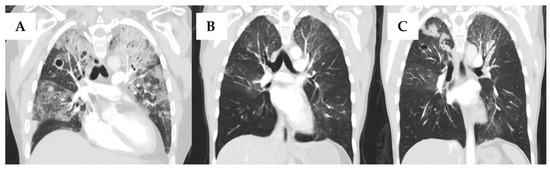

Figure 1.

Computed tomographic (CT) scans of the lung of a 42-year-old female with nontuberculous mycobacterial infection (NTM) and non-Aspergillus invasive mold infection (NAMI) in a hematopoietic cell transplant recipient, who subsequently received bilateral lung transplantation. (A) Multifocal ground-glass opacities more prominent in the left lung; 1.5 cm cavitary lesion in the right upper lobe with centrilobular nodularity reported prior to NTM and NAMI therapy initiation. (B) Near-complete clearing of severe bilateral airspace consolidations after treatment of Microascus spp. and Mycobacterium chimaera infections. (C) Bilateral consolidative changes in the upper lobes, mostly at the time of diagnosis of Aspergillus calidoustus infection.